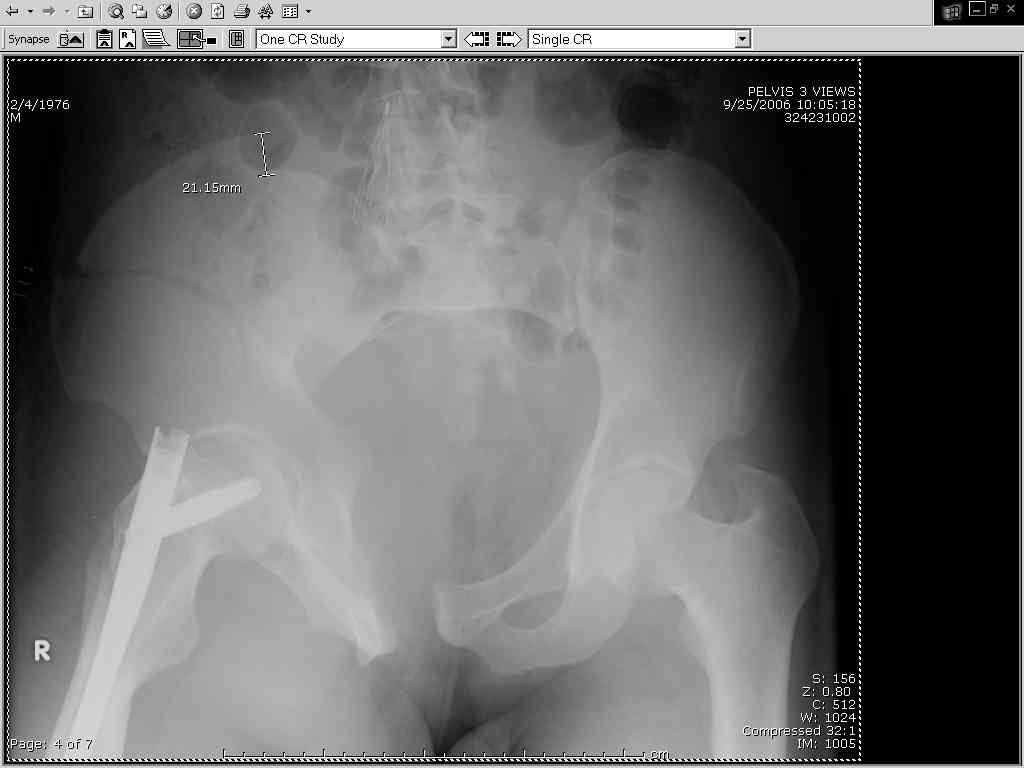

Dear colleagues, Please see attached 30 y.o. male with APC III pelvis s/p 25' fall 3d ago.

planning ORIF tomorrow via symph/ilioinguinal R and either perc or ORIF L SI disloc. femur Fx already fixed by someone else, and pelvis not put in traction or otherwise stabilized. advice on approach and order of fixation (SI first, symph first? R iliac wing?) appreciated. will go all anterior for simplicity, single position, etc. Jeff Brooks